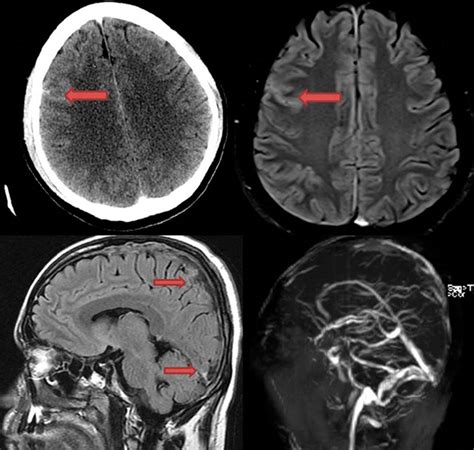

When blood leaks into the subarachnoid space, it appears as a bright, high-density (white) area on the scan, contrasting sharply with the darker, fluid-filled ventricles and brain tissue. The sensitivity of the scan is paramount; modern multidetector scanners are capable of detecting even very small amounts of subarachnoid blood. However, as time passes from the initial hemorrhage, the sensitivity of the scan decreases as the blood begins to dilute or break down.

The Importance of CT Angiography (CTA)

While the initial Subarachnoid Hemorrhage CT is used to detect the presence of blood, it does not always reveal the source of the bleeding. Once a hemorrhage is confirmed, clinicians typically transition to a CT Angiography (CTA). This procedure uses a contrast dye injected into the bloodstream to create detailed, three-dimensional images of the brain's vascular structure. The goal of the CTA is to identify the underlying cause, such as an aneurysm, which may require surgical clipping or endovascular coiling.

The transition from a standard scan to an angiographic scan is seamless in most modern facilities. The vascular imaging allows neurosurgeons and interventional neuroradiologists to plan the necessary interventions immediately. Understanding the vascular map is essential for preventing re-bleeding, which carries a much higher mortality rate than the initial event.